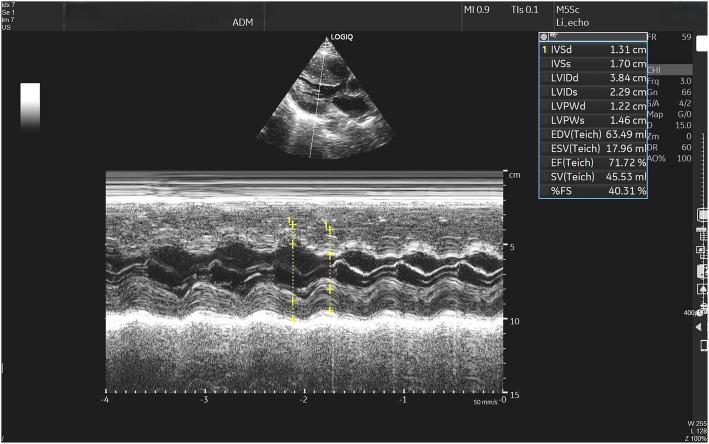

The patient presented with a 10-month history of recurrent chest tightness and shortness of breath, with symptoms significantly worsening 6 hours before admission. She was diagnosed with acute heart failure in the decompensated phase, complicated by cardiogenic shock. Stabilization was achieved via an intra-aortic balloon pump (IABP) and veno-arterial extracorporeal membrane oxygenation (VA-ECMO). Further evaluation revealed pheochromocytoma as the underlying cause of acute heart failure. The patient underwent successful surgical resection of the pheochromocytoma, with no recurrence of heart failure symptoms observed during follow-up.

该患者有10个月反复胸闷、气短病史,入院前6小时症状明显加重。她被诊断为失代偿期急性心力衰竭,并发心源性休克。通过主动脉内球囊反搏(IABP)和静脉-动脉体外膜肺氧合(VA-ECMO)实现了病情稳定。进一步评估发现嗜铬细胞瘤是急性心力衰竭的潜在病因。患者成功接受了嗜铬细胞瘤手术切除,随访期间未观察到心力衰竭症状复发。